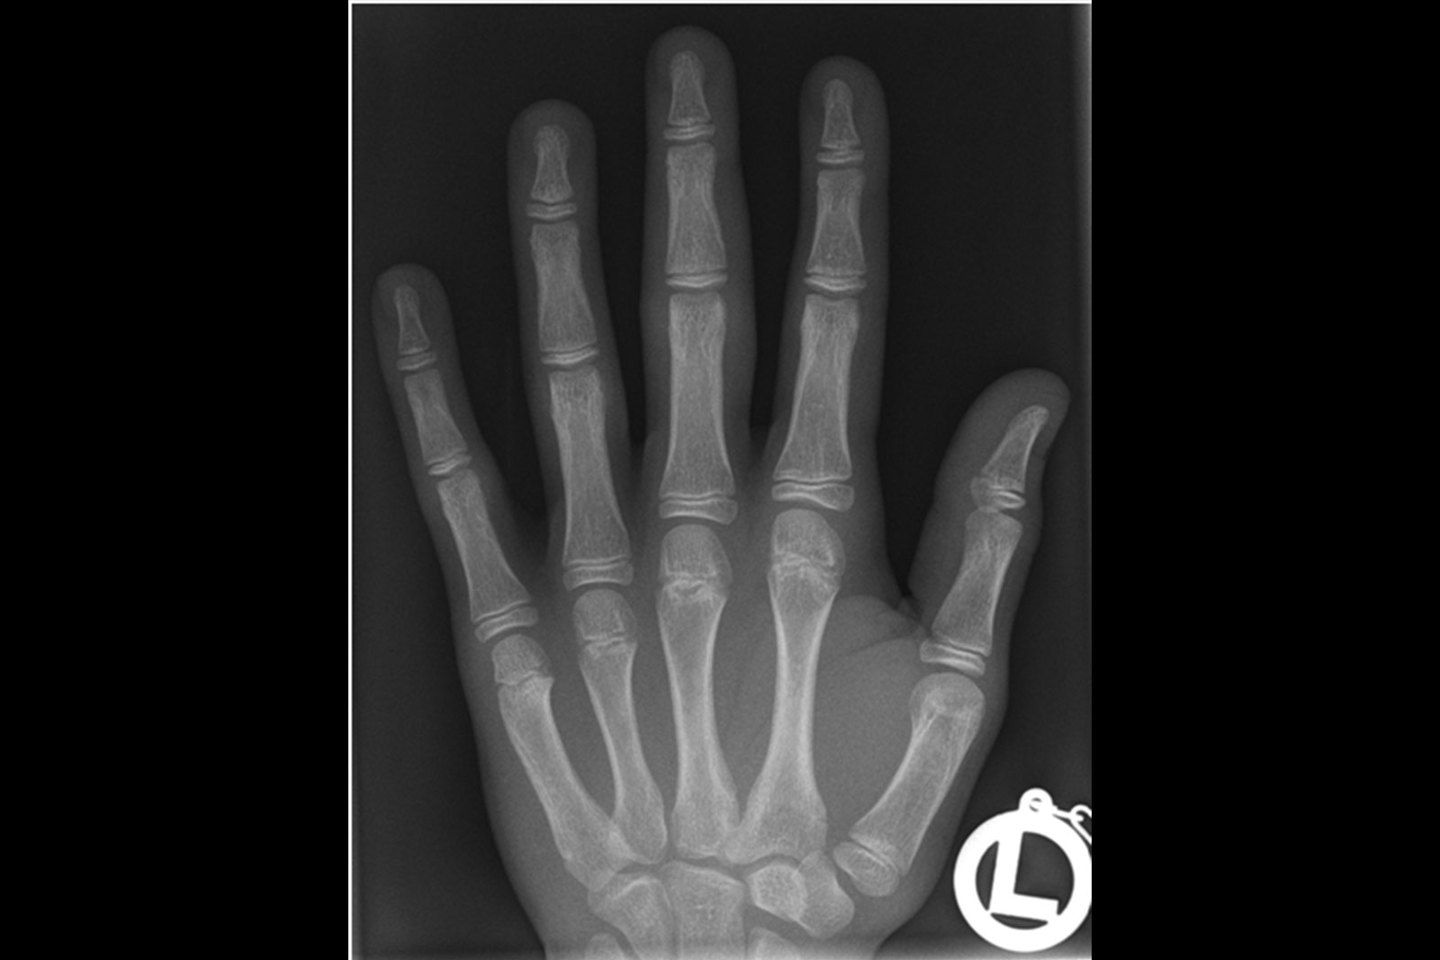

Zo ziet een foto van de binnenkant van je hand eruit.

This is what a photograph of the inside of your hand/wrist looks like.